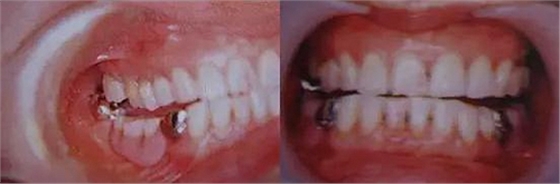

圖10. 不考慮下頜第三磨牙的咬合平面破壞的修復(fù)體制作完成后,

后方磨牙干擾引發(fā)的前方誘導(dǎo)干擾。